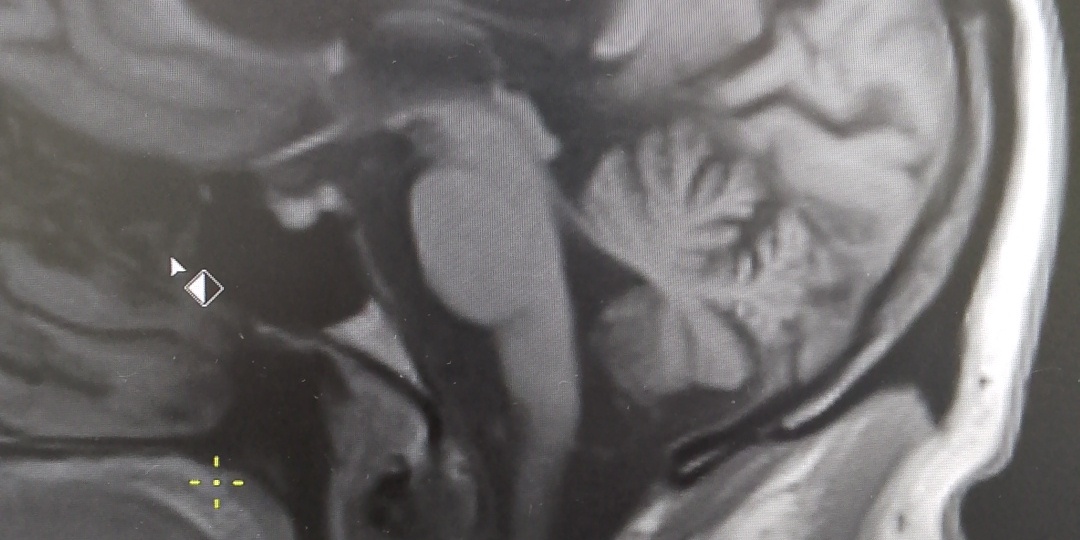

Шатает в стороны, нарушилась координация движений, плывет картинка перед глазами- иногда не так просто собрать пазл точного диагноза при таких жалобах В феврале у меня были трое пациентов 50+, у которых это все было + у кого то были иные жалобы, но течение их заболевания не было похоже на выше описанное ПППГ и причина была другая- дегенеративное заболевание головного мозга. Это группа заболеваний с прогрессирующим течением, построенным нарастанием симптомов На самом деле, эта тройка симптомов - повод , чтобы врачу в поиске диагноза следовать "от общего к частному" и такие ощущения вполне могут быть проявлениями анемии, сердечно- сосудистых заболеваний. Слишком они не специфичны Но есть отдельная группа неврологических заболеваний - дегенеративные заболевания нервной системы. Начало может быть с такими симптомами, но с особенностями, иногда, яркими, а иногда менее заметными ✅ Прогрессирующее течение- за год- два симптомы нарастают ✅ Шаткость сопровождается падениями, которые могут